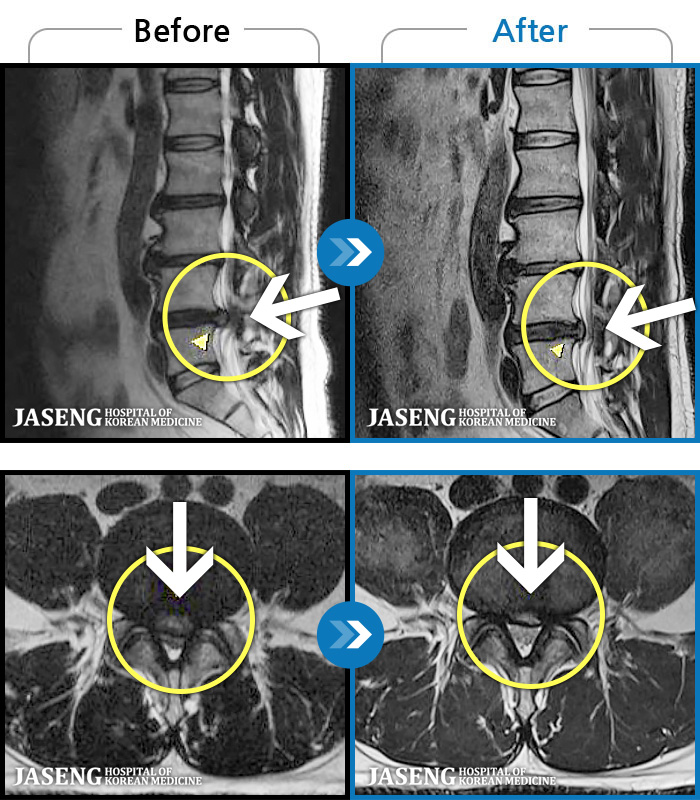

- MRI ġ

MRI ġ

1,240 MRI ũ ʸ Ȯϼ.